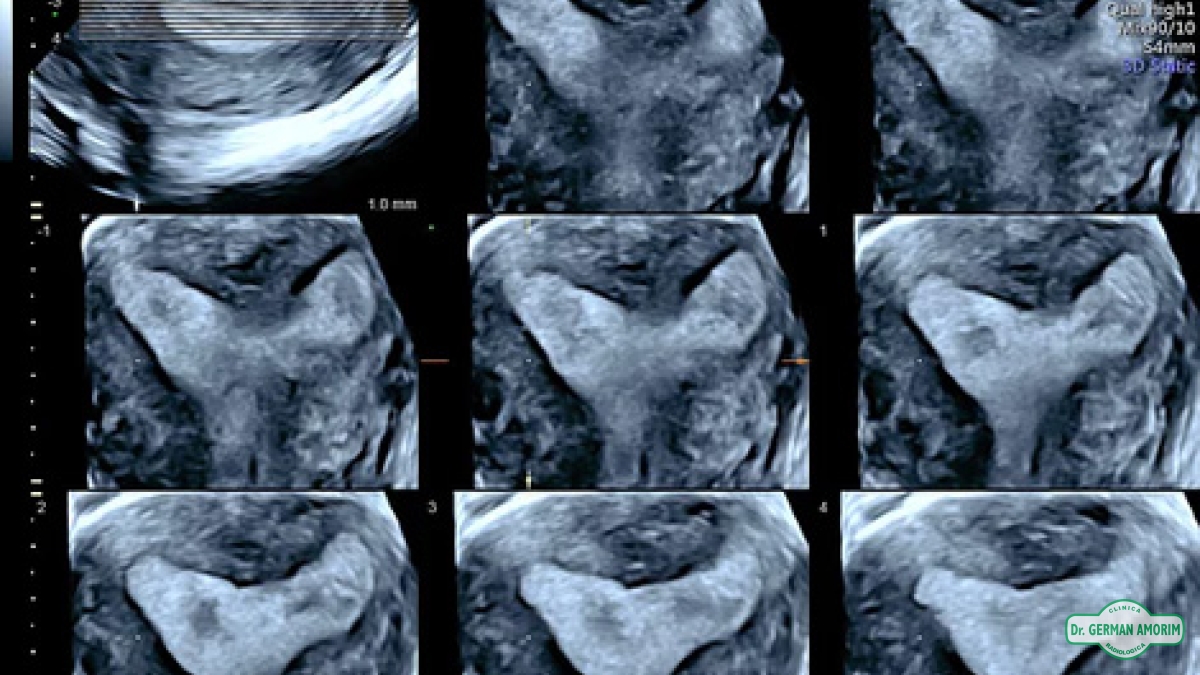

Equipo de Alta Gama Multiproposito para todo tipo de estudios, calidad de imagen superior para el diagnóstico preciso, 4D/5D con HD Live para imágenes del feto únicas color natural, Doppler de.

• Confianza con excelentes imágenes 2D y 3D / 4D, optimizadas para claridad y detalle.

Las demandas de los pacientes y las presiones de tiempo son altas. Para tener éxito, su práctica requiere imágenes excepcionales y eficientes, lo que le ayuda a proporcionar respuestas a sus pacientes mientras administra su práctica ocupada. Con herramientas de automatización fáciles de usar, puede optimizar su flujo de trabajo, disminuir la complejidad del examen y aumentar la consistencia. Las tecnologías de automatización de Sono de Voluson ayudan a mejorar la reproducibilidad delos exámenes obstétricos y ginecológicos a la vez que documentan con fines de garantía de calidad, lo que le ayuda a lograr más cada día y le permite brindar la mejor atención de la SERIE SIGNA TURE a sus pacientes.

Cálculos automáticos en Obstetricia, cálculo de folículos, imagen única en Mamas para diagnóstico eficiente, posibilidad de elastografia, cálculos automáticos en Mama etc.